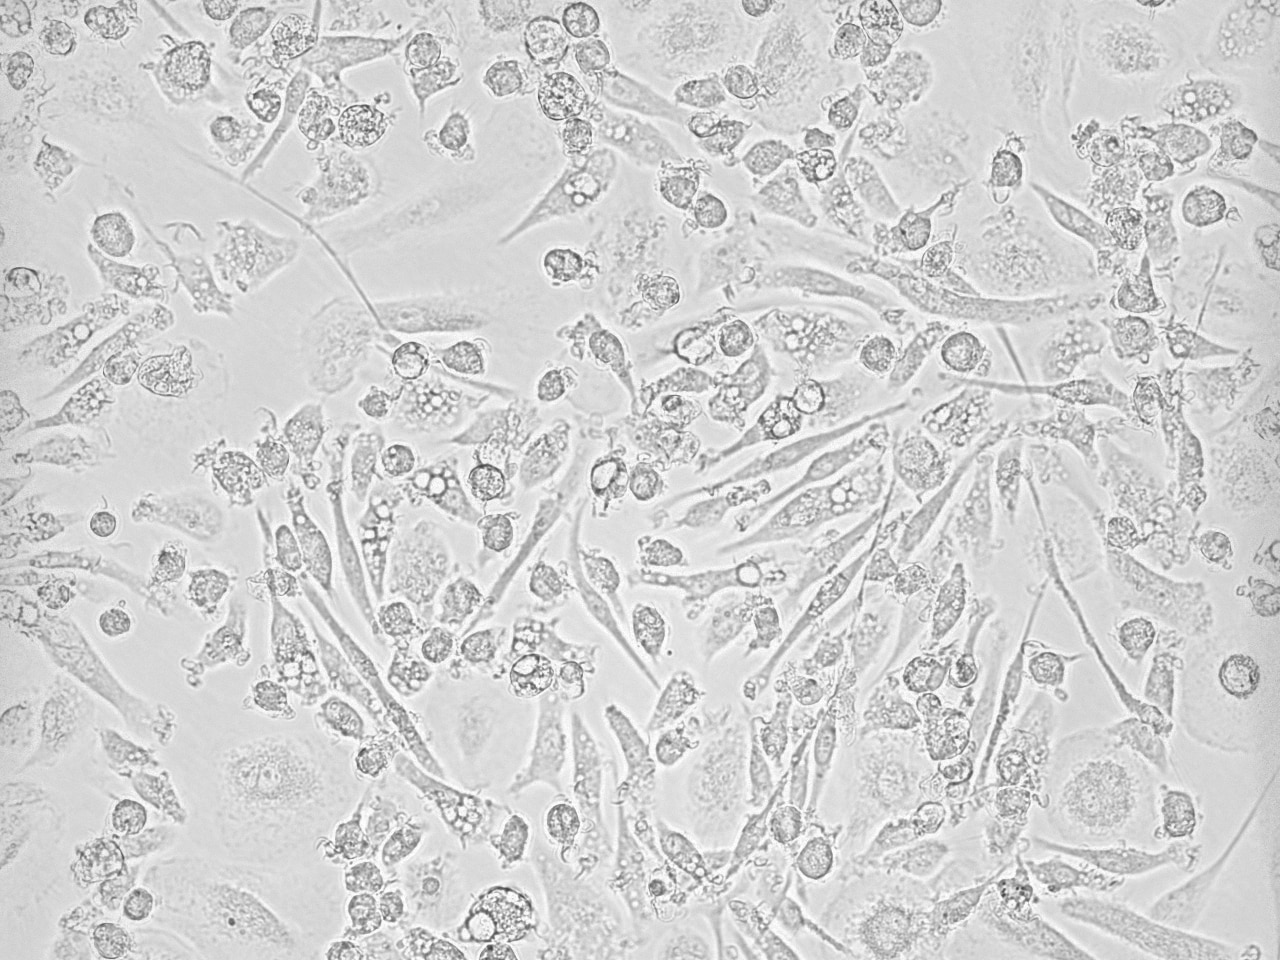

FH Federico (Verified Customer) (12-22-2025) | It works perfectly. I use it in culture media to generate macrophages or microglia from hiPSCs.

FH Lucy (Verified Customer) (11-07-2025) | I used this product to differentiate monocyte-derived macrophages and they looked beautiful! Really pleased with the performance of this product.

FH Ariane (Verified Customer) (03-28-2025) | Used it to promote macrophage growth from bone marrow derived cells; used it at a conc. of 10ng/mL seems to work

FH Romane (Verified Customer) (12-06-2024) | Works great for differentiation of human iPSCs-derived macrophages